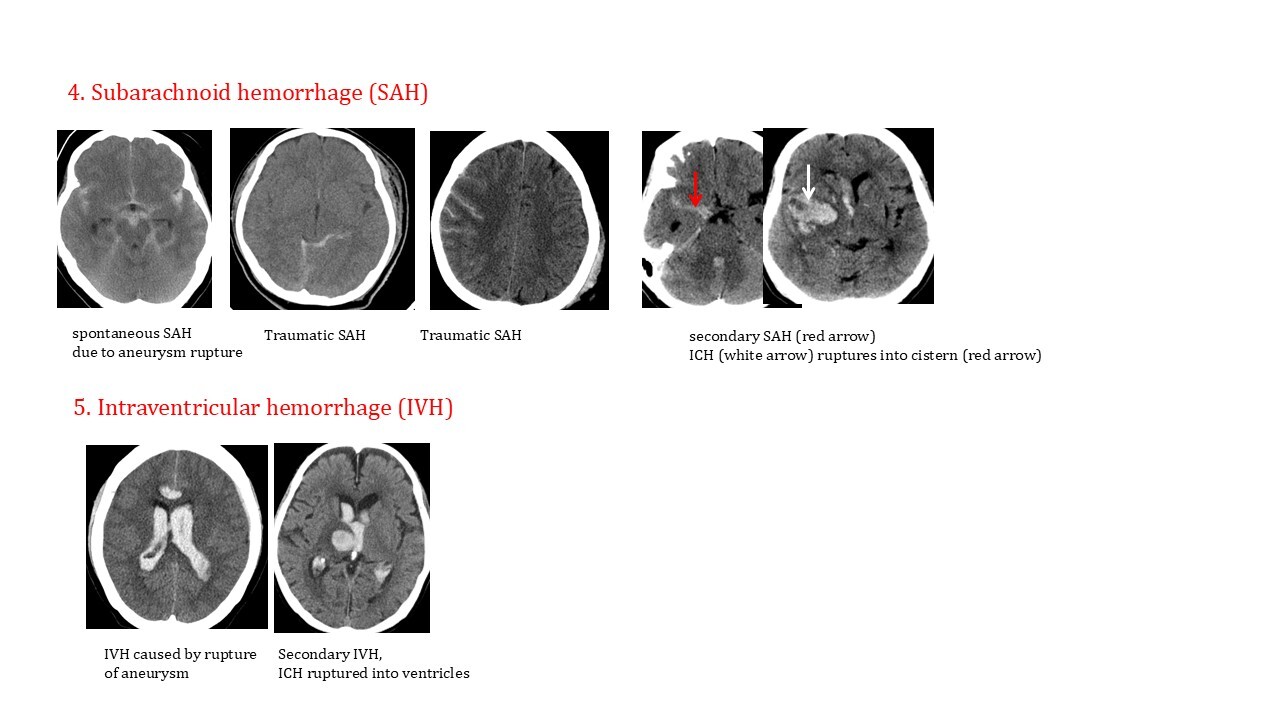

4. 蜘蛛網膜下腔出血Subarachnoid hemorrhage (SAH),因為不易形成血塊,所以叫hemorrhage,而不寫成subarachnoid hematoma。

SAH又分為:

A. 原發性(primary SAH) 或自發性(spontaneous SAH),主要是因動脈瘤破裂引起。

B. 次發性(secondary),即先有ICH,再流入蜘蛛網膜下腔。

C. 外傷性(traumatic SAH)是頭部外傷所引起。

5. 腦室內出血(intraventricular hemorrhage,IVH)。

IVH大多數是先有ICH再破入腦室內,或外傷性IVH,原發性IVH (primary IVH)發生率很低,AVM破裂是其中一項原因。